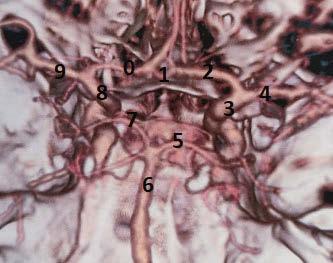

Uzupełnieniem diagnostyki w chorobach naczyniowych mózgowia jest badanie angiograficzne w tomografii komputerowej lub rezonansie magnetycznym, co obecnie stało się standardem postępowania w diagnostyce chorób naczyniowych, zwłaszcza w udarze niedokrwiennym mózgu. W związku z rozwojem interwencyjnego leczenia udaru badania angiograficzne są z powodzeniem wykorzystywane w wizualizacji zwężeń głównych osi naczyniowych zasilających koło tętnicze mózgu oraz okluzji jego części składowych i jego gałęzi jako badanie bezpośrednio poprzedzające trombektomię

mechaniczną w leczeniu ostrej fazy udaru niedokrwiennego mózgu. Do technik, dzięki którym można uzyskać wgląd w układ naczyniowy mózgowia, należy zaliczyć również angiografię klasyczną oraz subtrakcyjną.

Rycina 1.36. Obraz naczyń koła tętniczego i jego gałęzi uzyskany w angio-TK, rekonstrukcja 3D VR (Volume Rendering). Na obrazie niewidoczne są obie tętnice łączące tylne (hipoplastyczne). 1 – tętnica łącząca przednia; 2 – tętnica przednia mózgu lewa; 3 – tętnica szyjna wewnętrzna lewa; 4 – tętnica środkowa mózgu lewa; 5 – tętnica tylna mózgu lewa; 6 – tętnica podstawna; 7 – tętnica tylna mózgu prawa; 8 – tętnica szyjna wewnętrzna prawa; 9 – tętnica środkowa mózgu prawa; 10 – tętnica przednia mózgu prawa.